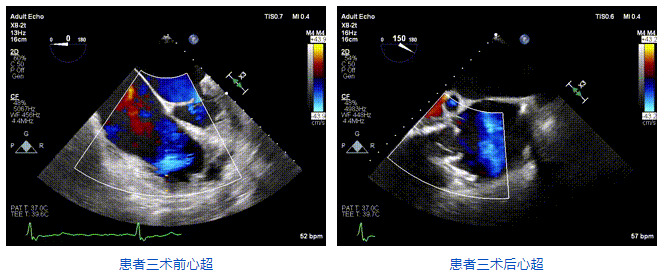

2021年12月24日,復(fù)旦大學(xué)附屬中山醫(yī)院葛均波院士團隊成功應(yīng)用LuX-Valve Plus為一例極重度三尖瓣反流(TR)合并房顫、房缺的患者完成了經(jīng)血管三尖瓣置換術(shù),這是在前基礎(chǔ)上,本周完成的第三例經(jīng)血管三尖瓣置換手術(shù),葛均波院士、周達新教授等與心外科魏來教授、賴顥教授,心超室的潘翠珍教授、李偉教授及麻醉科的郭克芳教授共同完成了本周手術(shù),均獲得圓滿成功!患者術(shù)后超聲顯示無TR,臨床癥狀明顯改善。本周手術(shù)的成功也為LuX-Valve Plus救治性臨床研究添上了濃墨重彩的一筆。

三例患者入院后,葛均波院士團隊周達新教授、潘文志教授、張源博士、陳莎莎博士及心超室的潘翠珍教授、李偉教授對患者的情況進行詳細評估和討論,最終決定為三例患者選擇LuX-Valve Plus40mm、50mm和50mm型號的瓣膜進行手術(shù)治療。手術(shù)后即刻拔除氣管插管,術(shù)后患者三尖瓣反流癥狀得到顯著改善,復(fù)查心超結(jié)果顯示人工三尖瓣瓣膜支架固定穩(wěn)定,瓣葉關(guān)閉形態(tài)未見異常,未見明顯反流。